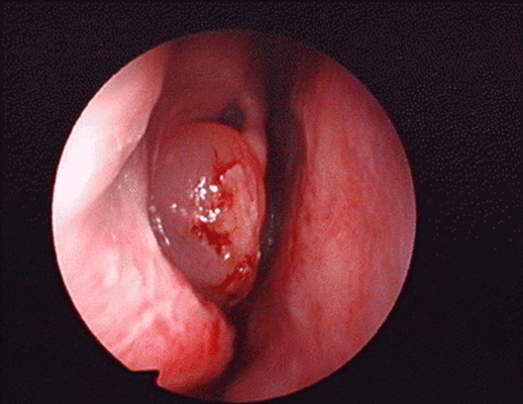

鼻息肉是耳鼻喉科常见病症之一,与部分全身性疾病也存在关联。它本质上是鼻黏膜长期受炎症刺激导致组织水肿、逐渐下垂形成的良性肿物。外观多呈灰白、淡黄或淡红色,形似荔枝肉,表面光滑,半透明,多发生于中鼻道、窦口及筛窦区域,严重时可堵塞鼻腔,影响呼吸与嗅觉。

•鼻内镜下鼻内病损微创切除术:适用于鼻腔鼻窦多发息肉。该术式借助鼻内窥镜精细操作,能充分开放窦腔、彻底摘除息肉。我院近年来开展的鼻内镜微创手术,具有精细、准确、创伤小、恢复快的优势,能显著降低术后复发率。